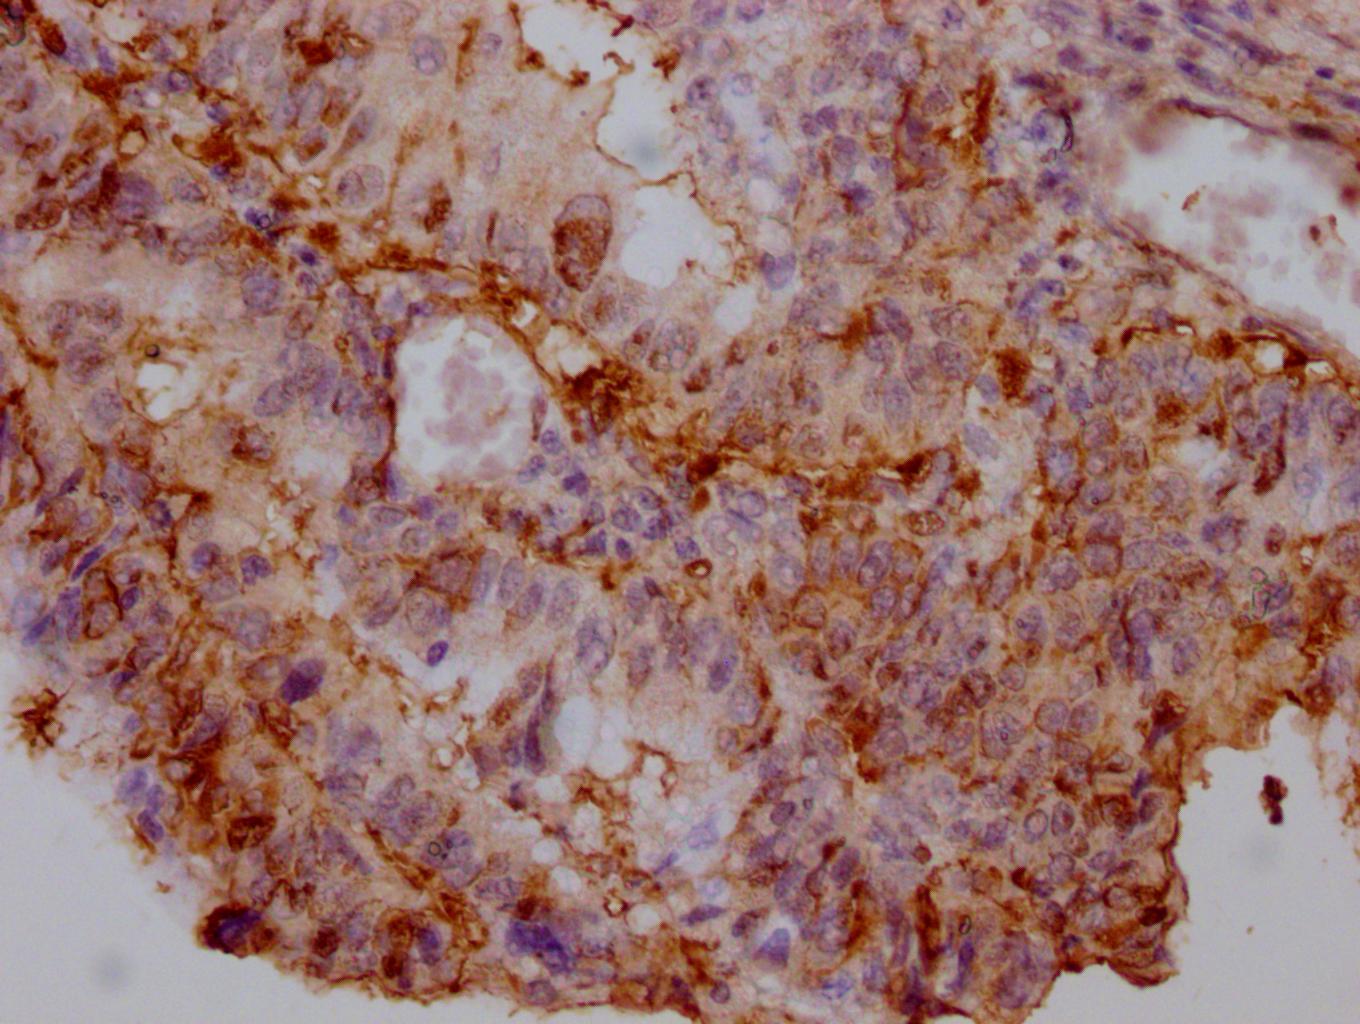

IHC image of CSB-MA007670A0m diluted at 1:500 and staining in paraffin-embedded human colon cancer tissue performed on a Leica BondTM system. After dewaxing and hydration, antigen retrieval was mediated by high pressure in a citrate buffer (pH 6.0). Section was blocked with 10% normal goat serum 30min at RT. Then primary antibody (1% BSA) was incubated at 4°C overnight. The primary is detected by a biotinylated secondary antibody and visualized using an HRP conjugated SP system.